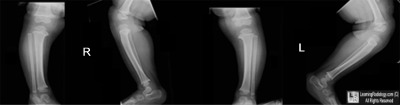

Case of the Week 547

• 4 year-old with bowlegs

Frontal and lateral views of both lower legs

3. Blount Disease

Blount Disease

• Growth disturbance in the proximal, medial, epiphyseal plate, epiphysis, and metaphysis of the tibia produces medial angulation (varus deformity) at the knee and internal rotation of the tibia